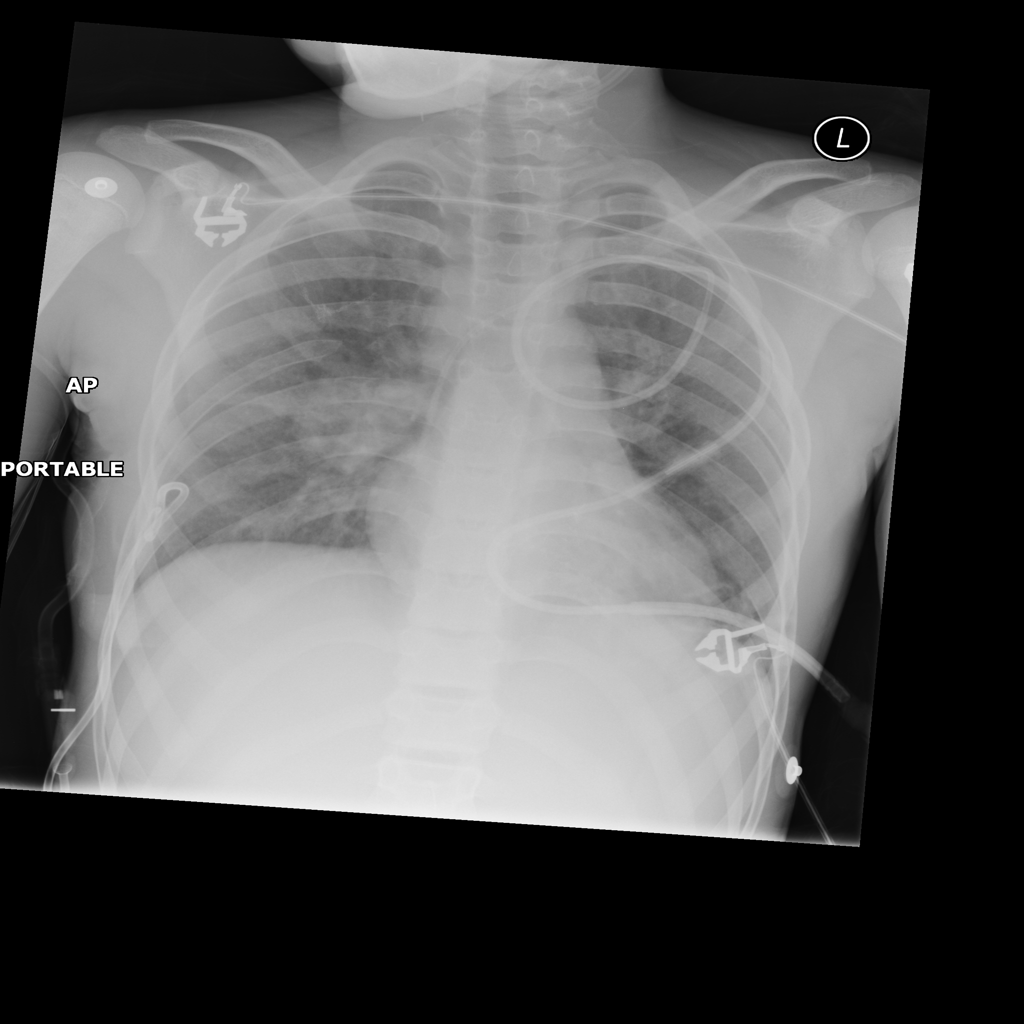

Mass

A mass is a larger focal opacity or lesion seen on the image. It is a descriptive finding that can have several causes and usually needs more imaging or clinical context to characterize.

PAT-4639 · IMG-024Mass

PAT-4639 · IMG-024

AP